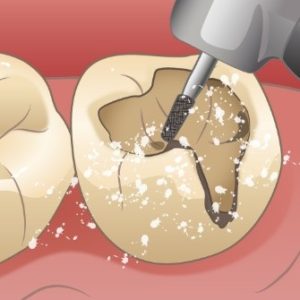

むし歯の治療

充填(コンポジットレジン修復など)

むし歯菌に感染した歯質を削ったところに合成樹脂(レジン)と無機フィラーとの複合材料であるコンポジットレジンという材料を詰めて治します。

↑むし歯がある状態 ↑むし歯を削ります ↑キレイに削りました

↑レジンを詰めていきます ↑光を当てて固めてから形を整えて完了です

インレー修復

むし歯菌に感染した歯質を削ったあとの穴にピッタリはまる修復物(インレー)を作り(削った穴の型をとり、石こうの模型にして口の外で作る)、その修復物(インレー)を削った穴に接着剤でくっつける。

↑むし歯がある状態 ↑むし歯を削ります ↑キレイに削りました

↑削った穴に合った修復物(インレー)を接着剤でくっつけて完了です!